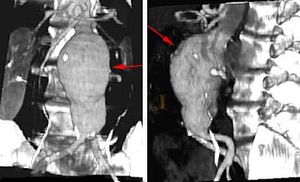

تمدد الأوعية الدموية Aneurysms هو إنتفاخ يشبه البالون في الشرايين، و يمكن أَن يتشكل في الشرايين بمختلف أحجامها. يحدث تمدد الأوعية الدموية عندما يجبر ضغط الدم، الذي يعبر جزء ضعيف من شريان ما، الجدران على الإنتفاخ للخارج. لا تعتبر كلّ حالات تمدد الأوعية الدموية خطرة. لكن إذا مدّت هذه الإنتفاخات الشريان بصورة ضخمة، فإن الجدران قد تنفجر، تاركة الشخص المصاب ينزف إلى الموت. تمدد الأوعية الدموية الذي يؤدي إلى نزيف في تجويف الدماغ يمكن أن يؤدي إلى الجلطة الدماغية أو الموت.

- في أجزاء الشريان الأبهر. الشريان الأبهر يحمل الدم من القلب إلى أجزاء أخرى من الجسم. تمدد الأوعية الدموية الأبهري يمكن أنْ يحدث في المنطقة أسفل المعدة (تمدد أوعية دموية بطني) أو في الصدر (تمدد أوعية دموية صدري). تمدد الأوعية الدموية البطني الأبهري يقع عادة تحت الكلى.

تمدد الأوعية الدموية يمكن أَنْ يكتشف بالفحص، بإستخدام صور الأشعة السينية للصدر أو للمعدة ، أَو بإستعمال التصوير بإستخدام النظائر المشعة أو الموجات فوق السمعية. يمكن أيضا أستعمال تصوير الرنين المغناطيسي، أو سي تي سكان tomographycomputed tomography (CT) scanning.

تعتمد المعالجة على حجم وموقع التمدد وصحة المصاب العامة. تمدد الأوعية الدموية في قسم الصدر الأعلى (الشريان الأبهر الصاعد) يخضع للجراحة فورا. تمدد الأوعية الدموية في القسم الصدري الأوطأ والمنطقة أسفل المعدة (أجزاء صدرية وبطنية من الشريان الأبهر) قد لا يشكل خطر يهدد حياة المصاب. التمدد في هذه المواقع يتم مراقبته بإنتظام. إذا وصل إلى قطر 5 سنتيمترات (تقريبا بوصتان)، أو واصل النمو، أو بدأ بالتسبّب بأعراض مزعجة، فيمكن اللجوء أيضا للجراحة لإيقاف تمدد الأوعية الدموية قبل إنفجارها.